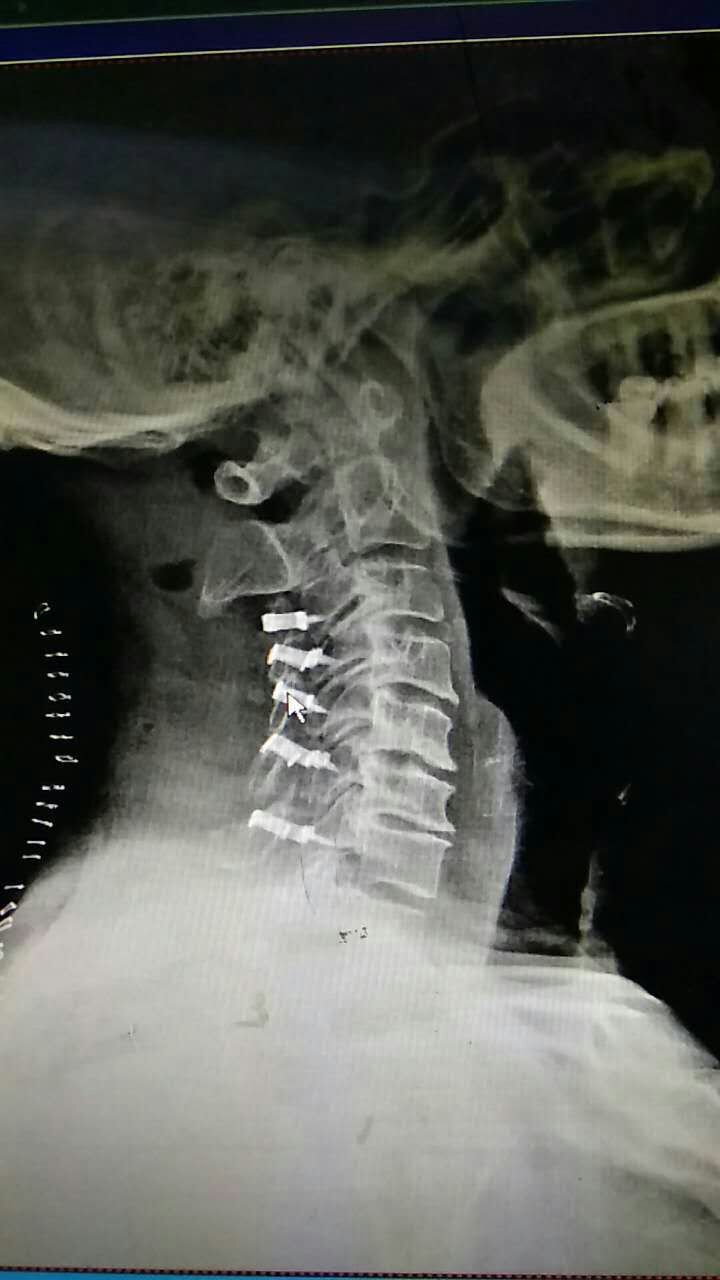

颈椎后路单开门手术 微型钛板固定优势多_好大

720x1280 - 55KB - JPEG